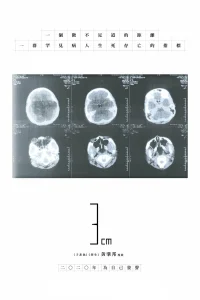

3cm

4.0

2019